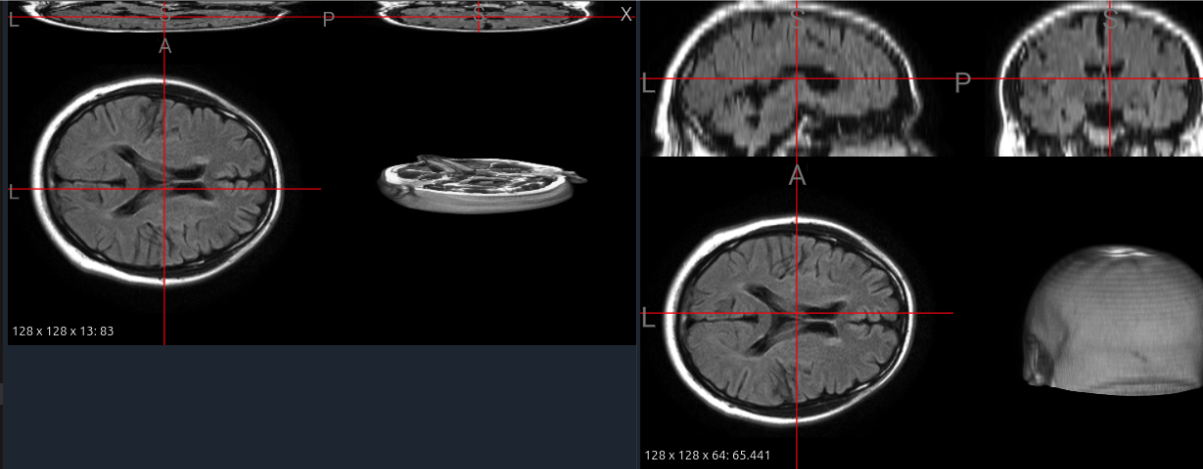

Figure 10 illustrates a FLAIR image from the MS-60 dataset before and after interpolation. The original scan (13 slices) shows severe discontinuities and collapsed tissue boundaries, whereas the interpolated version (64 slices) restores smoother cortical contours and continuous sulcal structures without distorting global shape. Quantitatively, the effective slice thickness decreased by approximately 4.8×\times, enabling isotropic patch extraction for pretraining and consistent input dimensions across datasets.

From a foundation model perspective, interpolation functions as a structural equalizer: it harmonizes volumetric resolution across sources, improving patch uniformity and kernel receptive fields. However, it also generates synthetic voxels that may obscure very small hyperintensities or produce interpolation artifacts along lesion edges. Thus, interpolation should be applied selectively—preferably on high-anisotropy datasets or in conjunction with uncertainty-aware augmentations—to balance geometric consistency and lesion fidelity.

Refer to caption

Figure 10: Interpolation of a FLAIR image from the MS-60 dataset. Left: original thin-slice volume (13 slices) showing discontinuities. Right: interpolated volume (64 slices) with improved z-axis continuity and preserved anatomy.